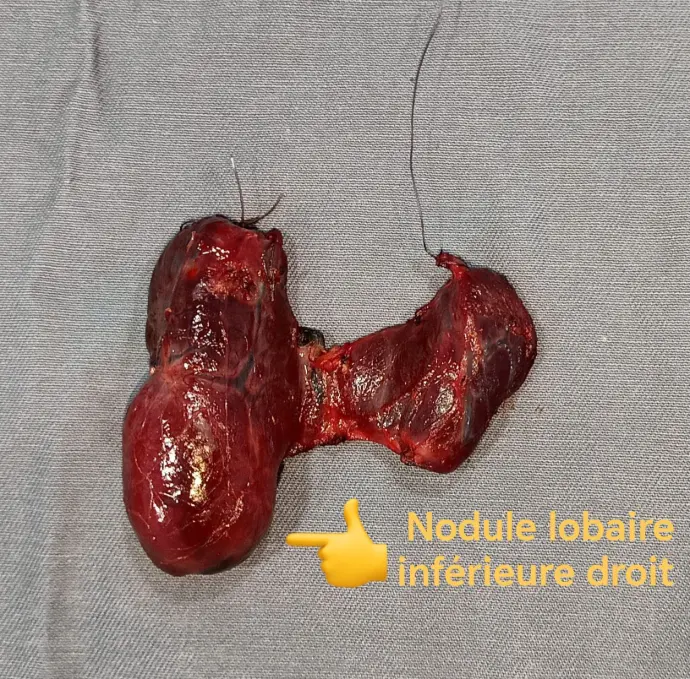

4. العقد الدرقية (Thyroid Nodules):

تكون كتل صغيرة داخل الغدة الدرقية.

غالبًا ما تكون حميدة، لكنها تحتاج إلى الفحص لاستبعاد السرطان.

3. تضخم الغدة الدرقية (Goiter):

تضخم في حجم الغدة الدرقية.

قد يكون بسبب نقص اليود أو مشاكل أخرى مثل العقيدات الدرقية.